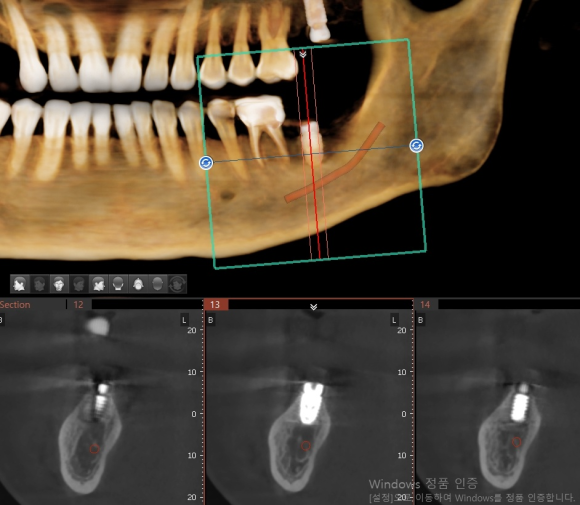

인천에서 오신 분 내과 당일 협진으로 전신 질환 (당요 등등) 확인 후 임플란트 식립. 뼈가 좋지 않아서 충분하게 분석 후 신경 손상을 피하기 위해 전략적이로 보수적으로 접근. 수술 후 3D 사진을 이용한 확인 완료. #상도동에서임플란트가장많이하는치과, #숭실대치과, #상도동치과, #동작구치과, #임플란트,...

인천에서 오신 분 내과 당일 협진으로 전신 질환 (당요 등등) 확인 후 임플란트 식립.

뼈가 좋지 않아서 충분하게 분석 후 신경 손상을 피하기 위해 전략적이로 보수적으로 접근.

수술 후 3D 사진을 이용한 확인 완료.